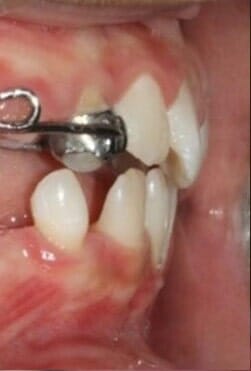

במקרים שבהם הלסת העליונה אחורית ללסת התחתונה ניתן למשוך את הלסת העליונה קדימה בצורה אופטימלית תוך הפיכת הניבים הנשירים לשתלים אורתודונטיים נספגים מעצמם. ד"ר גלעד הר- ציון הוא אחד מהאורתודונטים הבודדים בישראל אשר משתמשים ומיומנים בשיטה זו, אשר מביאה לתוצאות טובות גם במקרים קשים במיוחד.

לסת עליונה אחורית ביחס ללסת תחתונה

אחרי

לסת עליונה קידמת ביחס ללסת התחתונה אחרי

לפני

לסת עליונה קידמת ביחס ללסת התחתונה לפני